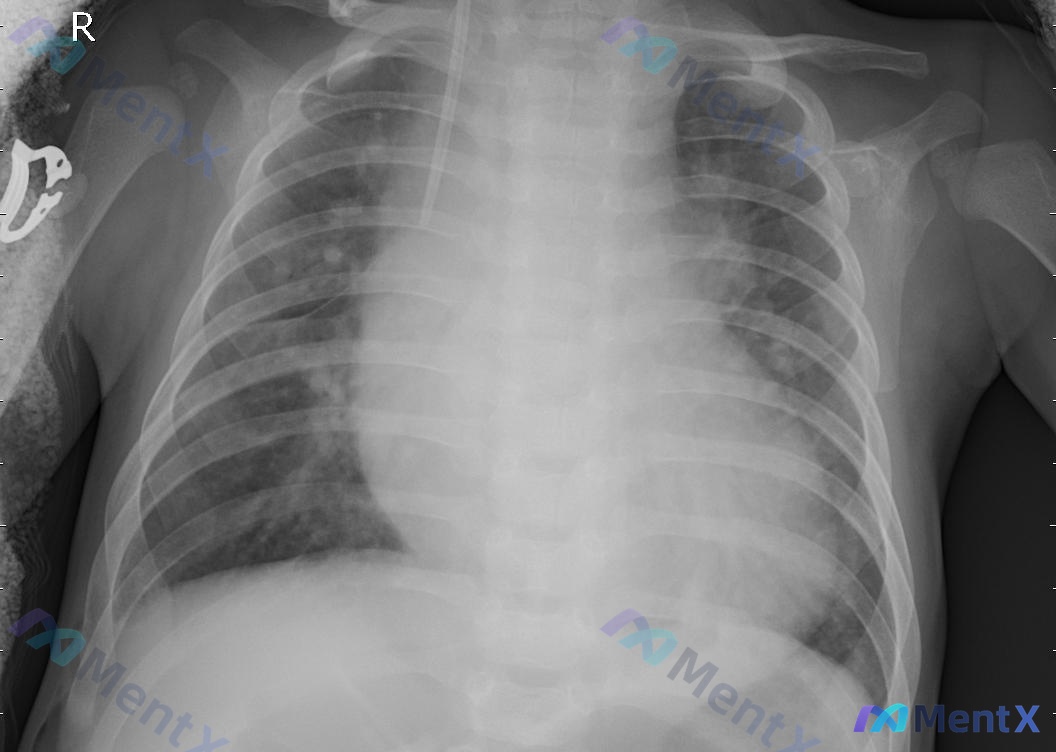

整理到一份仰卧位(AP位)胸部X光片的资料,几个核心征象先放出来: 1. 心影明显增大,呈球形,心胸比超过0.5 2. 双肺纹理增多模糊,弥漫斑片状、云絮状高密度影,下肺野明显 3. 双侧肋膈角变钝,提示胸腔积液 4. 可见一根中心静脉导管(CVC),尖端在右心房入口附近 第一眼可能会优先考虑什么?...

整理到一张胸部正位X光片(AP位,床旁拍摄)的分析资料,先抛出来大家一起理思路: 核心背景与影像 - 拍摄条件:床旁AP位,提示患者可能为卧床/重症状态 - 影像核心发现: - 双肺纹理增多、增粗、紊乱,以双侧中下肺野明显 - 双肺野(尤其中下肺)可见散在斑片状、云絮状高密度渗出影,边缘模糊 - 肺...